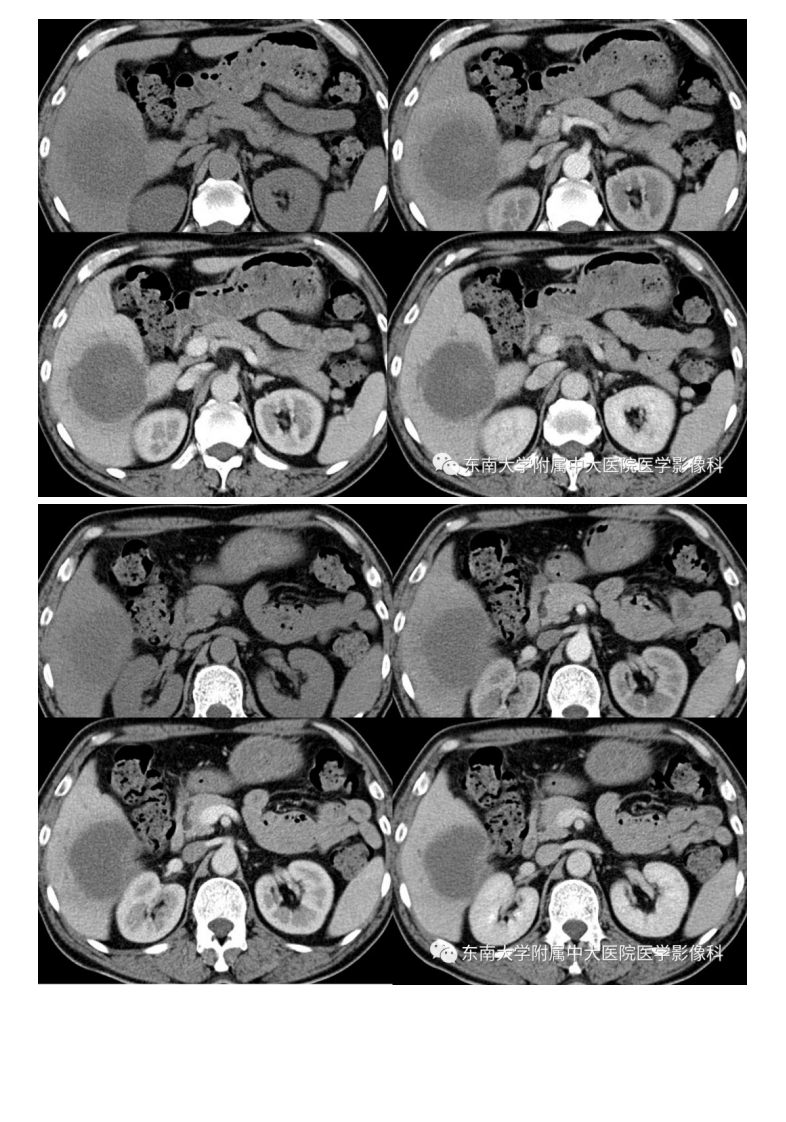

中大放射

20191230_2【晨读结果公布】2019.12.30消化系统疾病.pdf